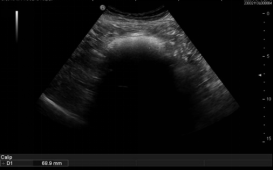

1,2  上消化道对比造影示:胃内充盈缺损影,大小约10.7x5.7cm,可随体位变化移动,考虑胃石。